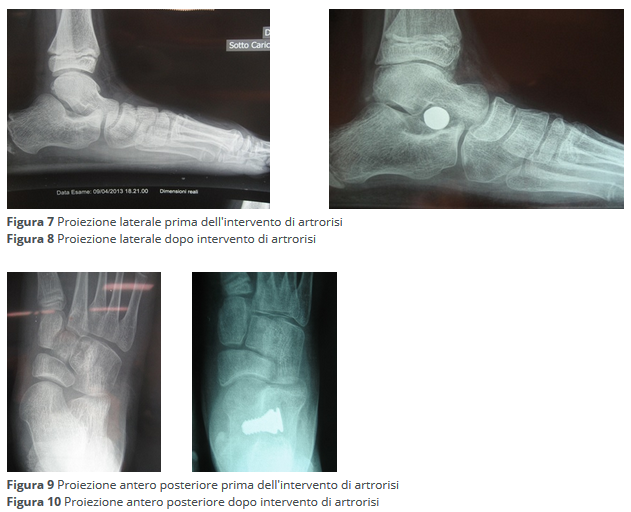

Nelle forme  in cui il piede valgo pronato non è correggibile manualmente ma in cui la deformità è meno grave, l'intervento chirurgico prevede l'applicazione di una vite (intervento di artrorisi) che ha lo scopo di evitare l'eccessiva pronazione e di risollevare l'arco plantare (Figure 7, 8, 9, 10). Nelle forme più gravi, in una fascia di età superiore ai tredici anni, si eseguono interventi di osteotomia ed artrodesi (Figure 11, 12, 13, 14).